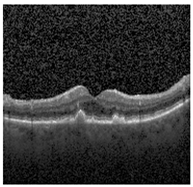

The publicly accessible dataset [27] encompasses detailed cross-sectional images of living patients’ retinas, which have been classified into four distinct categories: Normal, CNV, Drusen, and DME. These categories are visually represented in Figure 3. The dataset comprises a grand total of 84,492 images, distributed as follows: CNV contains 37,457 images, Normal contains 26,567 images, DME includes 11,600 images, and Drusen encompasses 8868 images.

Figure 3. Illustrative examples from the retinal image dataset are presented. Figure (a) showcasing Choroidal NeoVascularization, characterized by the presence of neovascular membranes (indicated by white arrowheads) along with associated sub-retinal fluid (marked by arrows). Figure (b) illustrates Diabetic Macular Edema, which manifests as intra-retinal fluid associated with retinal thickening (denoted by arrows). Figure (c) displays multiple instances of drusen (highlighted by arrowheads), while Figure (d) illustrates a normal, pristine retina with an undisturbed foveal structure and no signs of retinal fluid or edema.